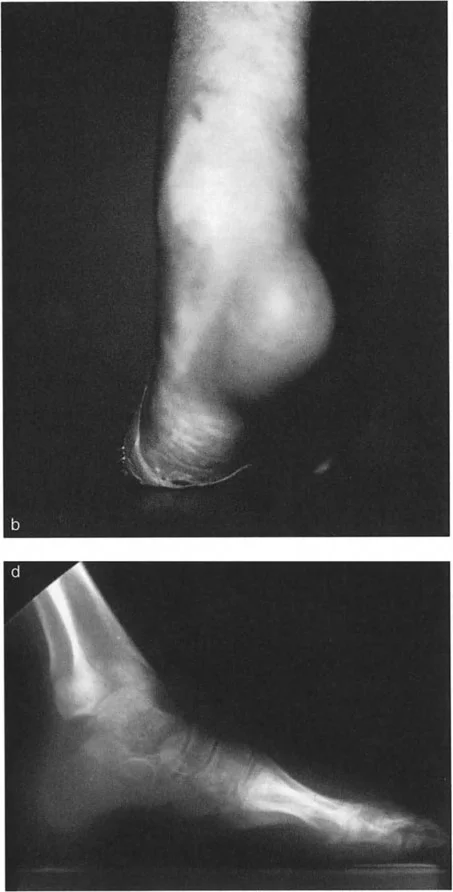

تغير شكل القدم والكاحل

• تشوه مرئي: في كثير من الحالات، يكون التشوه واضحًا للعين المجردة. قد يظهر الكاحل منحرفًا إلى الداخل (تقوس) أو إلى الخارج (روحبة).

• تشوه التقوس (Varus): يبدو الكاحل والقدم منحرفين إلى الداخل، مما يجعل القدم تبدو ذات قوس عالٍ (قدم جوفاء). هذا يسبب ضغطًا زائدًا على الحافة الخارجية للقدم.

• تشوه الروحبة (Valgus): يبدو الكاحل والقدم منحرفين إلى الخارج، مما يؤدي إلى تسطح قوس القدم (قدم مسطحة مرنة). هذا يزيد الضغط على الجانب الخارجي لمفصل الكاحل.

• تغير في شكل القدم: تتكيف القدم مع تشوه الساق للحفاظ على استواء السطح السفلي على الأرض. في تشوه التقوس، قد تصبح القدم صلبة وذات قوس عالٍ. في تشوه الروحبة، قد تتسطح القدم وتصبح مرنة.

* تقييم تعويضات القدم: يتم تقييم كيف تحاول القدم تعويض التشوه في الساق. على سبيل المثال، في تشوه التقوس الساقي، قد تظهر القدم بقوس عالٍ وصلب. في تشوه الروحبة، قد تظهر القدم مسطحة ومرنة.